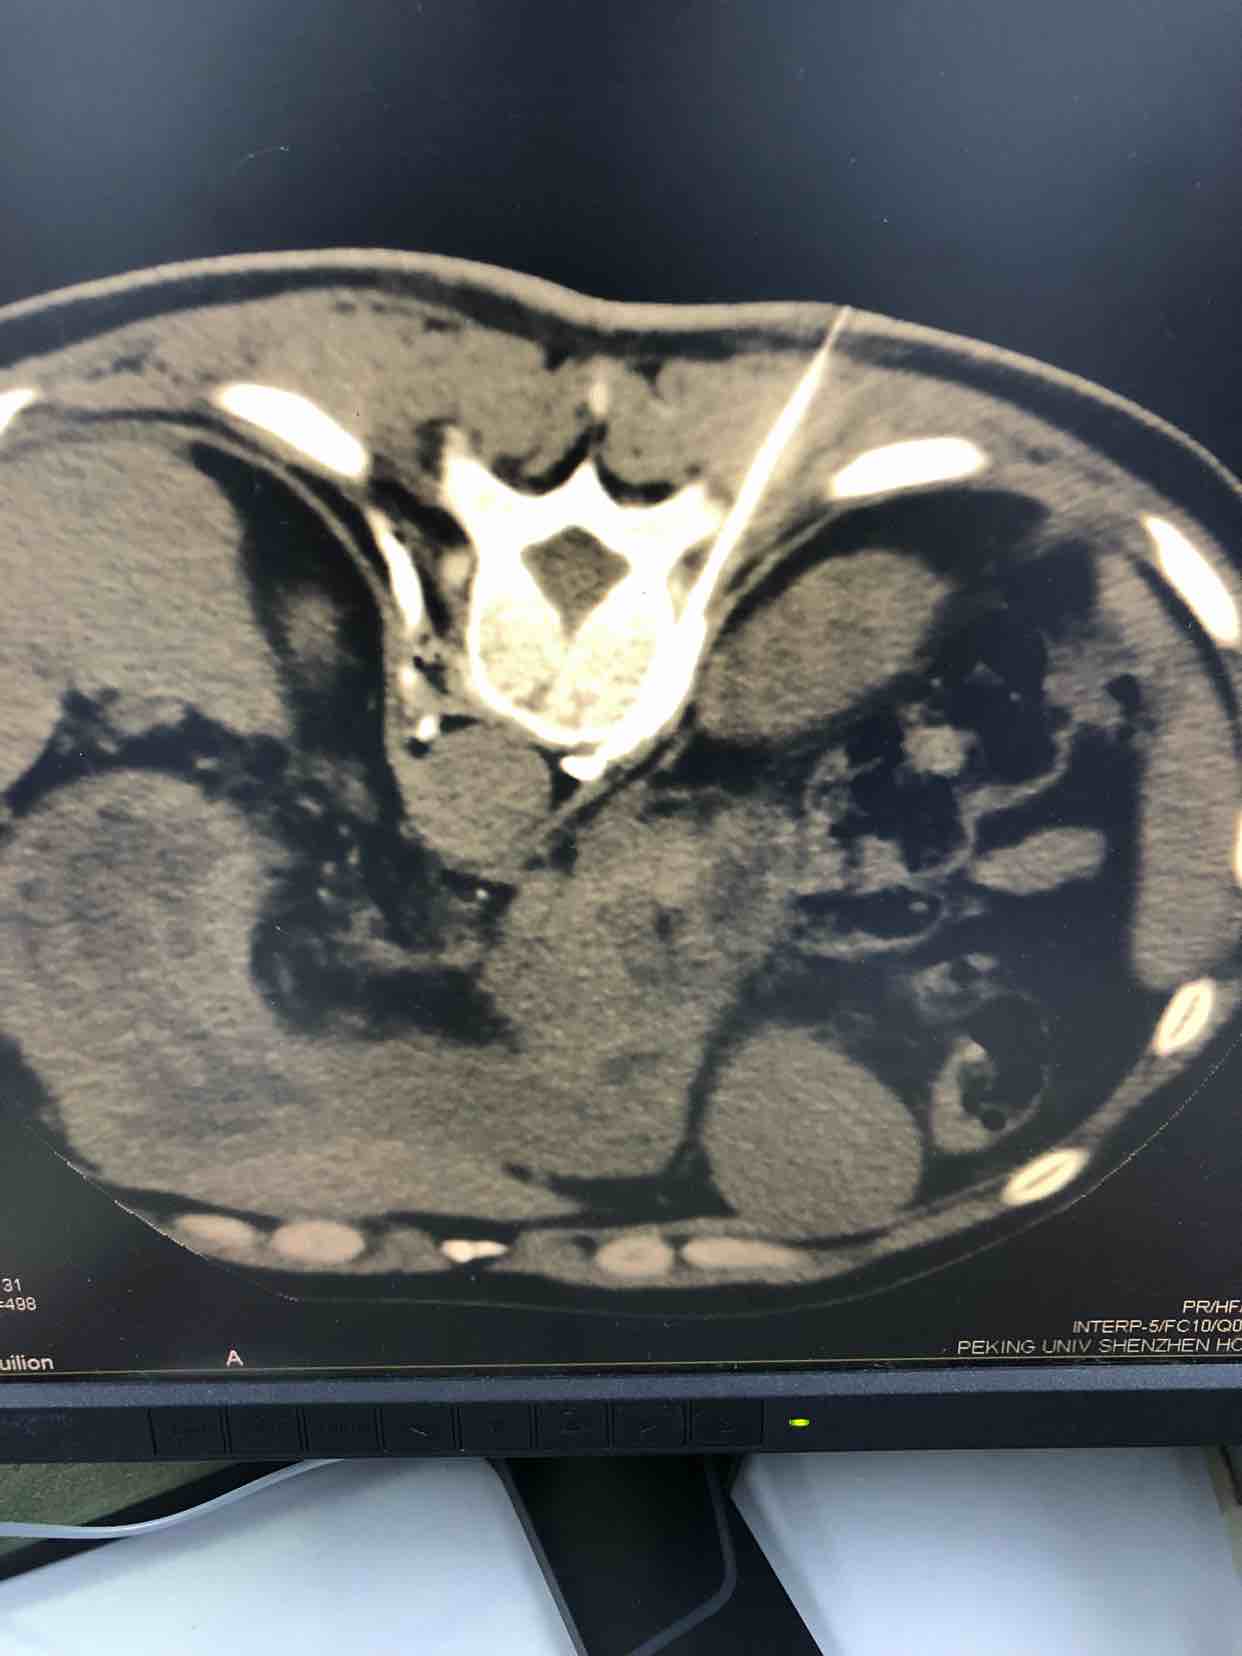

在上述规范化治疗下,仍旧有部分患者(10-20%)无法取得满意的止痛效果或者治疗中会出现恶心呕吐、便秘等严重影响生活质量的药物不良反应。我们把这部分疼痛定义为难治性癌痛。基于上述情况,癌痛治疗的”第四阶梯”陆续被相关学者关注和提出,包括患者自控镇痛、椎体成形术、神经毁损治疗、脊髓电刺激植入、鞘内吗啡泵植入等多种治疗方案。根据不同的癌痛类型我们可以选择不同的治疗方案,如胰腺癌、胃癌、肝癌等上腹部疼痛患者,我们选择在x光透视下行上腹腔神经丛的毁损治疗,整个过程只需要两根细小的穿刺针约半个小时的时间即可完成,全程无痛苦。对于盆腹腔内肿瘤如子宫内膜癌、宫颈癌、前列腺癌等下腹部疼痛,也可用上述方法行下腹腔神经丛毁损性治疗达到减少甚至停用吗啡用量的良好效果。